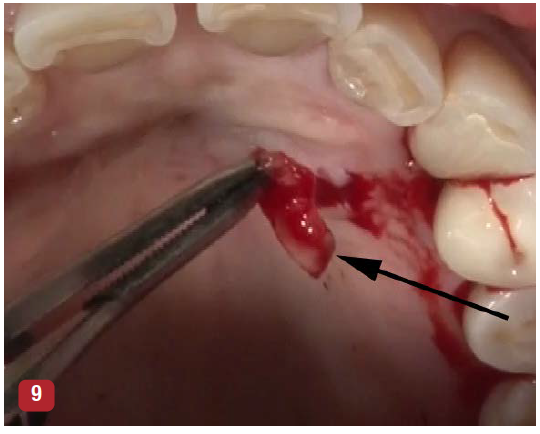

The incisions for VMIS around implants are similar to natural teeth but must be modified to accommodate the shape of the implant. A sulcular incision is made around the implant in the area of bone loss. The incision is extended to the mesial and distal as a split-thickness incision. This incision will extend to the line angle of adjacent teeth if present, or several millimeters into adjacent edentulous areas (Figure 8). A major difference in the use of VMIS on an implant is the removal of a section of connective tissue approximately 1-mm thick that is directly adjacent to the area of bone loss. Surgically, this is similar to the harvesting of a thin connective tissue graft (Figure 9). This step is performed to remove any microscopic particles of cement or titanium, which have been shown to penetrate the tissue and cause inflammation in cases of peri-implantitis.13